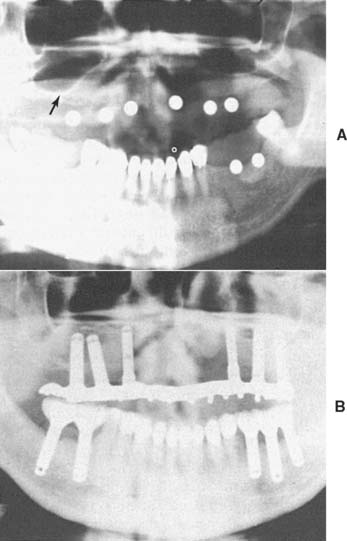

Radiographic evaluation is also necessary. The best initial film is the panoramic view. However, there can be variations in magnification (5% to 35%); a small radiopaque reference object should therefore be placed near the proposed implant placement site during the exposure (Fig. 13-5). Measurement of this image on the actual radiograph enables the practitioner to correct for any magnification error (Fig. 13-6). A ball bearing placed in wax on a denture baseplate or in polyvinyl siloxane impression putty works well. Some new panoramic radiography machines have standardized enlargement ratios, which makes correction markers less necessary.

Fig. 13-6 A panoramic radiograph exposed with the ball bearings positioned intraorally with a wax or resin baseplate.

The widths of the posterior mandible and maxilla are determined primarily by clinical examination. Bone width not revealed on a panoramic film can be evaluated in the anterior maxilla and mandible with a cephalometric film (Fig. 13-7). The location of the inferior alveolar canal and maxillary sinus can be determined by specialized computed tomography (CT) scans (Fig. 13-8), although high radiation exposure and considerable expense may limit their routine use. However, significant advances being made in this technology may change this trend.